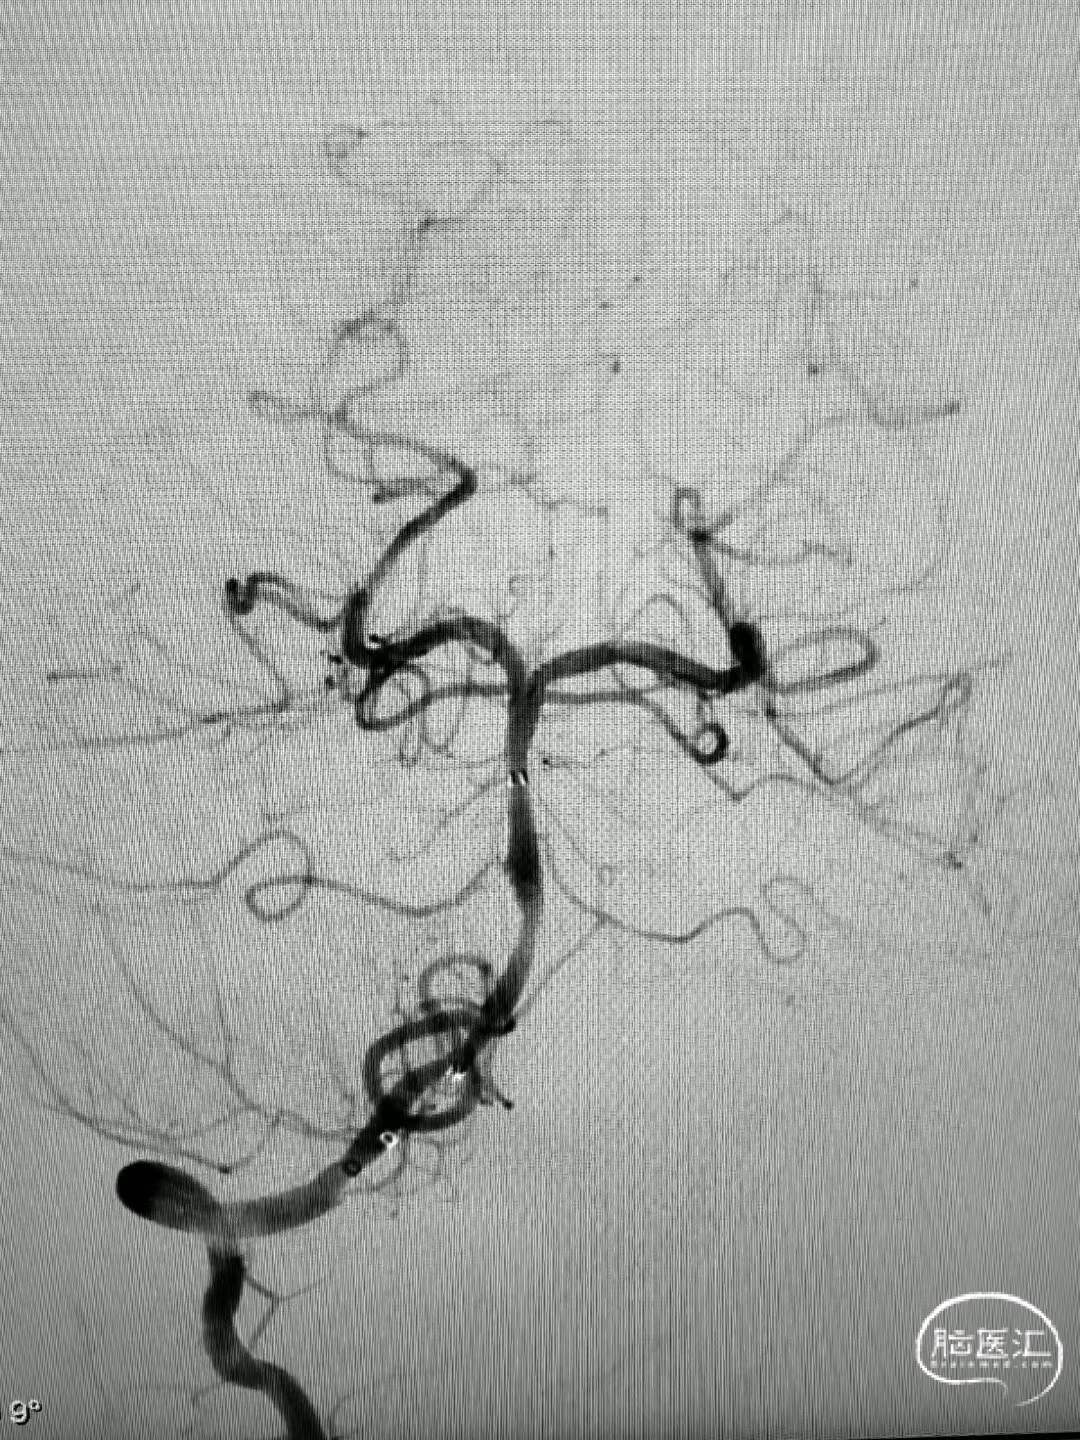

经肱动脉建立通路,抽吸,支架取出部分血栓,但考虑病变性质是夹层,血流无法维持,放置支架后基底动脉完全再通。

基底动脉完全再通,期待随访。